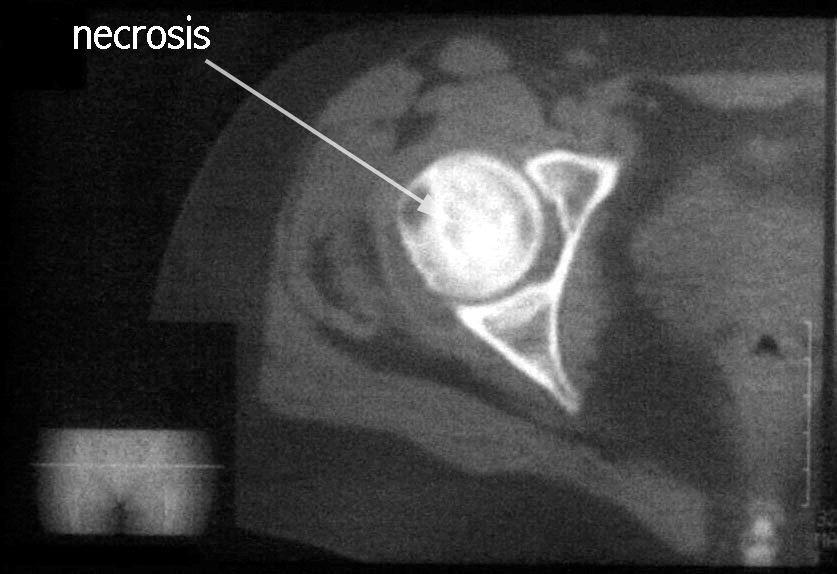

RADIOLOGIA

TOMOGRAFIA

RESONANCIA MAGNETICA  muy sensible a los cambios isquémicos tanto en zonas epifisarias como en zonas metafisodiafisarias.  diagnóstico precoz: 2-5 días.  El patrón de imagen puede variar según el grado de afectación y la respuesta individual.  Una doble linea entre el hueso isquemico y no isquemico.  correlación entre las imágenes de RMN y los hallazgos histopatológicos  Visualiza la integridad del cartílago articular y permite identificar cuerpos libres intraarticulares.